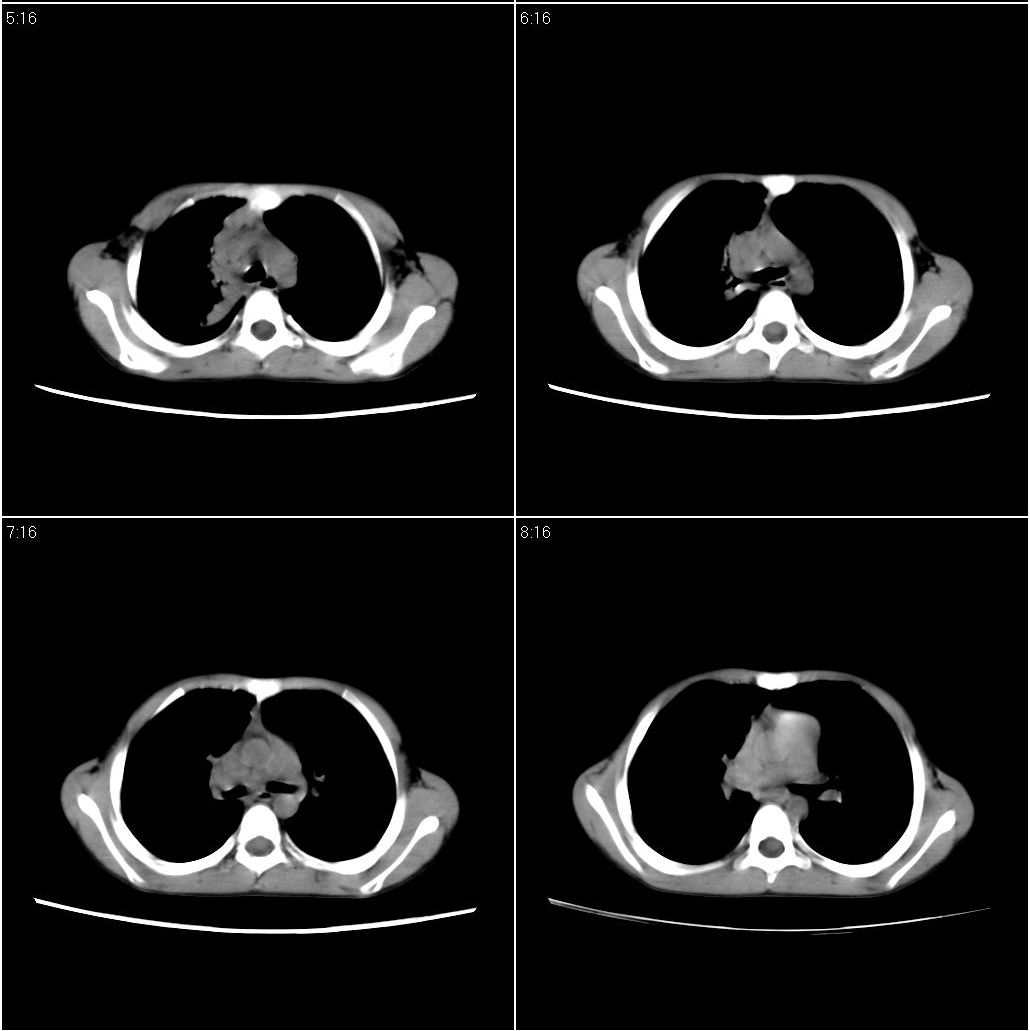

9月20号ct检查情况:

右上肺有班片状条索状高密度影。右肺上叶支气管稍变窄。右前上纵隔有结节状软组织密度影。上腔静脉旁淋巴结肿大。病灶抗炎后扩大。考虑结核可能性大。

考虑胸内淋巴结核

先考虑-----支气管淋巴结结核----查痰